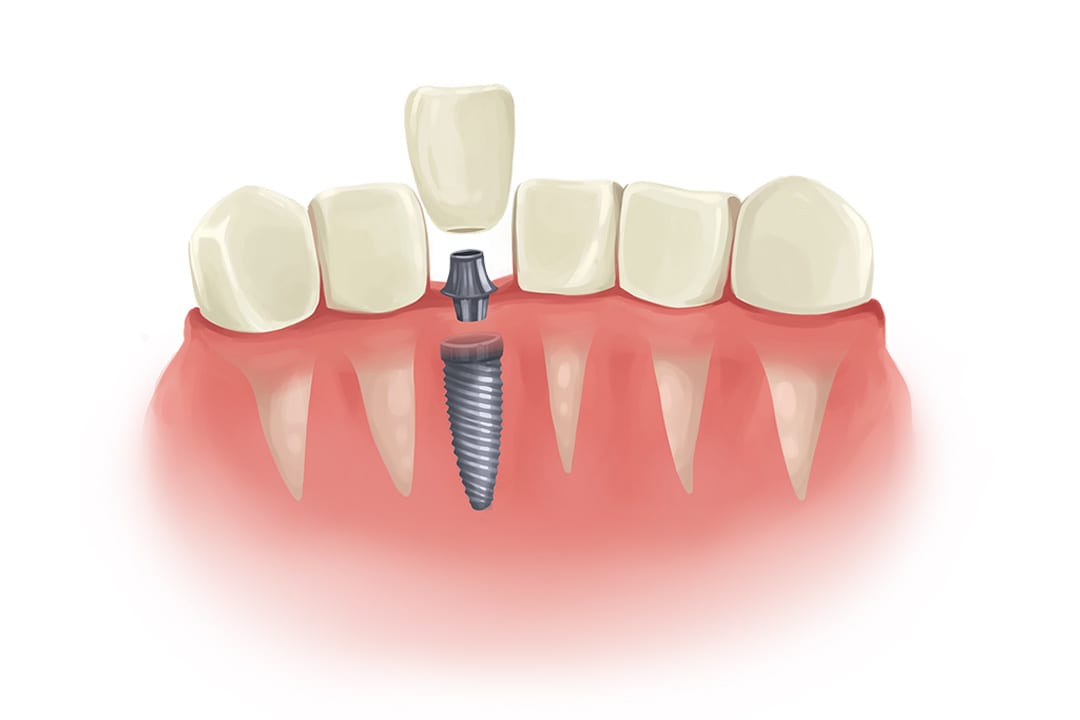

What are dental implants?

The long-term & effective solution for replacing missing teeth.

Dental implants are a long-term solution to missing teeth. When an adult tooth is lost, the area of jawbone that held the tooth begins to deteriorate. In preparation for a dental implant, a bone grafting procedure is typically done first. If all goes well, the bone graft and implant can last for a lifetime.

Dental implants are permanently situated in your mouth, so unlike dentures, they stay in place just like your own teeth. The root of the tooth is replaced by a screw, which becomes the artificial root. The screw sits in the jawbone and fuses with your jawbone, helped by the bone graft procedure.

There are different types of bone graft procedure available, depending on your needs. And there are also different approaches to the dental implants themselves, with the option for mini implants where standard ones can’t fit.